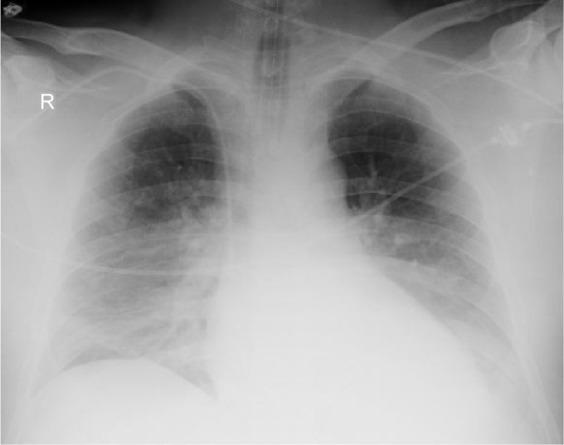

There are some patients with severe respiratory disturbances like adult respiratory distress syndrome (ARDS) and suspicion of brain death, for whom typical performance of the apneic test is difficult to complete because of quick desaturation and rapid deterioration without effective ventilation. To avoid failure of brain death confirmation and possible loss of organ donation another approach to apneic test is needed. We present two cases of patients with clinical symptoms of brain death, with lung pathology (acute lung injury, ARDS, lung embolism and lung infection), in whom apneic tests for recognizing brain death were difficult to perform. During typical performance of apneic test involving the use of oxygen catheter for apneic oxygenation we observed severe desaturation with growing hypotension and hemodynamic destabilization. But with the use of Boussignac CPAP system all necessary tests were successfully completed, confirming the patient's brain death, which gave us the opportunity to perform procedures for organ donation. The main reason of apneic test difficulties was severe gas exchange disturbances secondary to ARDS. Thus lack of positive end expiratory pressure during classical performance of apneic test leads to quick desaturation and rapid hemodynamic deterioration, limiting the observation period below dedicated at least 10-minute interval.

对于一些患有严重呼吸障碍(如成人呼吸窘迫综合征(ARDS))且疑似脑死亡的患者,由于在无有效通气的情况下快速出现血氧饱和度下降和病情迅速恶化,难以完成典型的 apnea 试验。为避免脑死亡确认失败以及可能导致的器官捐献损失,需要另一种进行 apnea 试验的方法。我们介绍两例有脑死亡临床症状且伴有肺部病变(急性肺损伤、ARDS、肺栓塞和肺部感染)的患者,在他们身上难以进行用于识别脑死亡的 apnea 试验。在涉及使用氧导管进行无呼吸氧合的典型 apnea 试验过程中,我们观察到严重的血氧饱和度下降,同时伴有低血压加重和血流动力学不稳定。但使用 Boussignac 持续气道正压通气(CPAP)系统后,所有必要的试验均成功完成,确认了患者的脑死亡,这使我们有机会进行器官捐献程序。apnea 试验困难的主要原因是继发于 ARDS 的严重气体交换障碍。因此,在经典的 apnea 试验过程中缺乏呼气末正压会导致快速的血氧饱和度下降和迅速的血流动力学恶化,将观察期限制在至少 10 分钟的规定间隔以下。